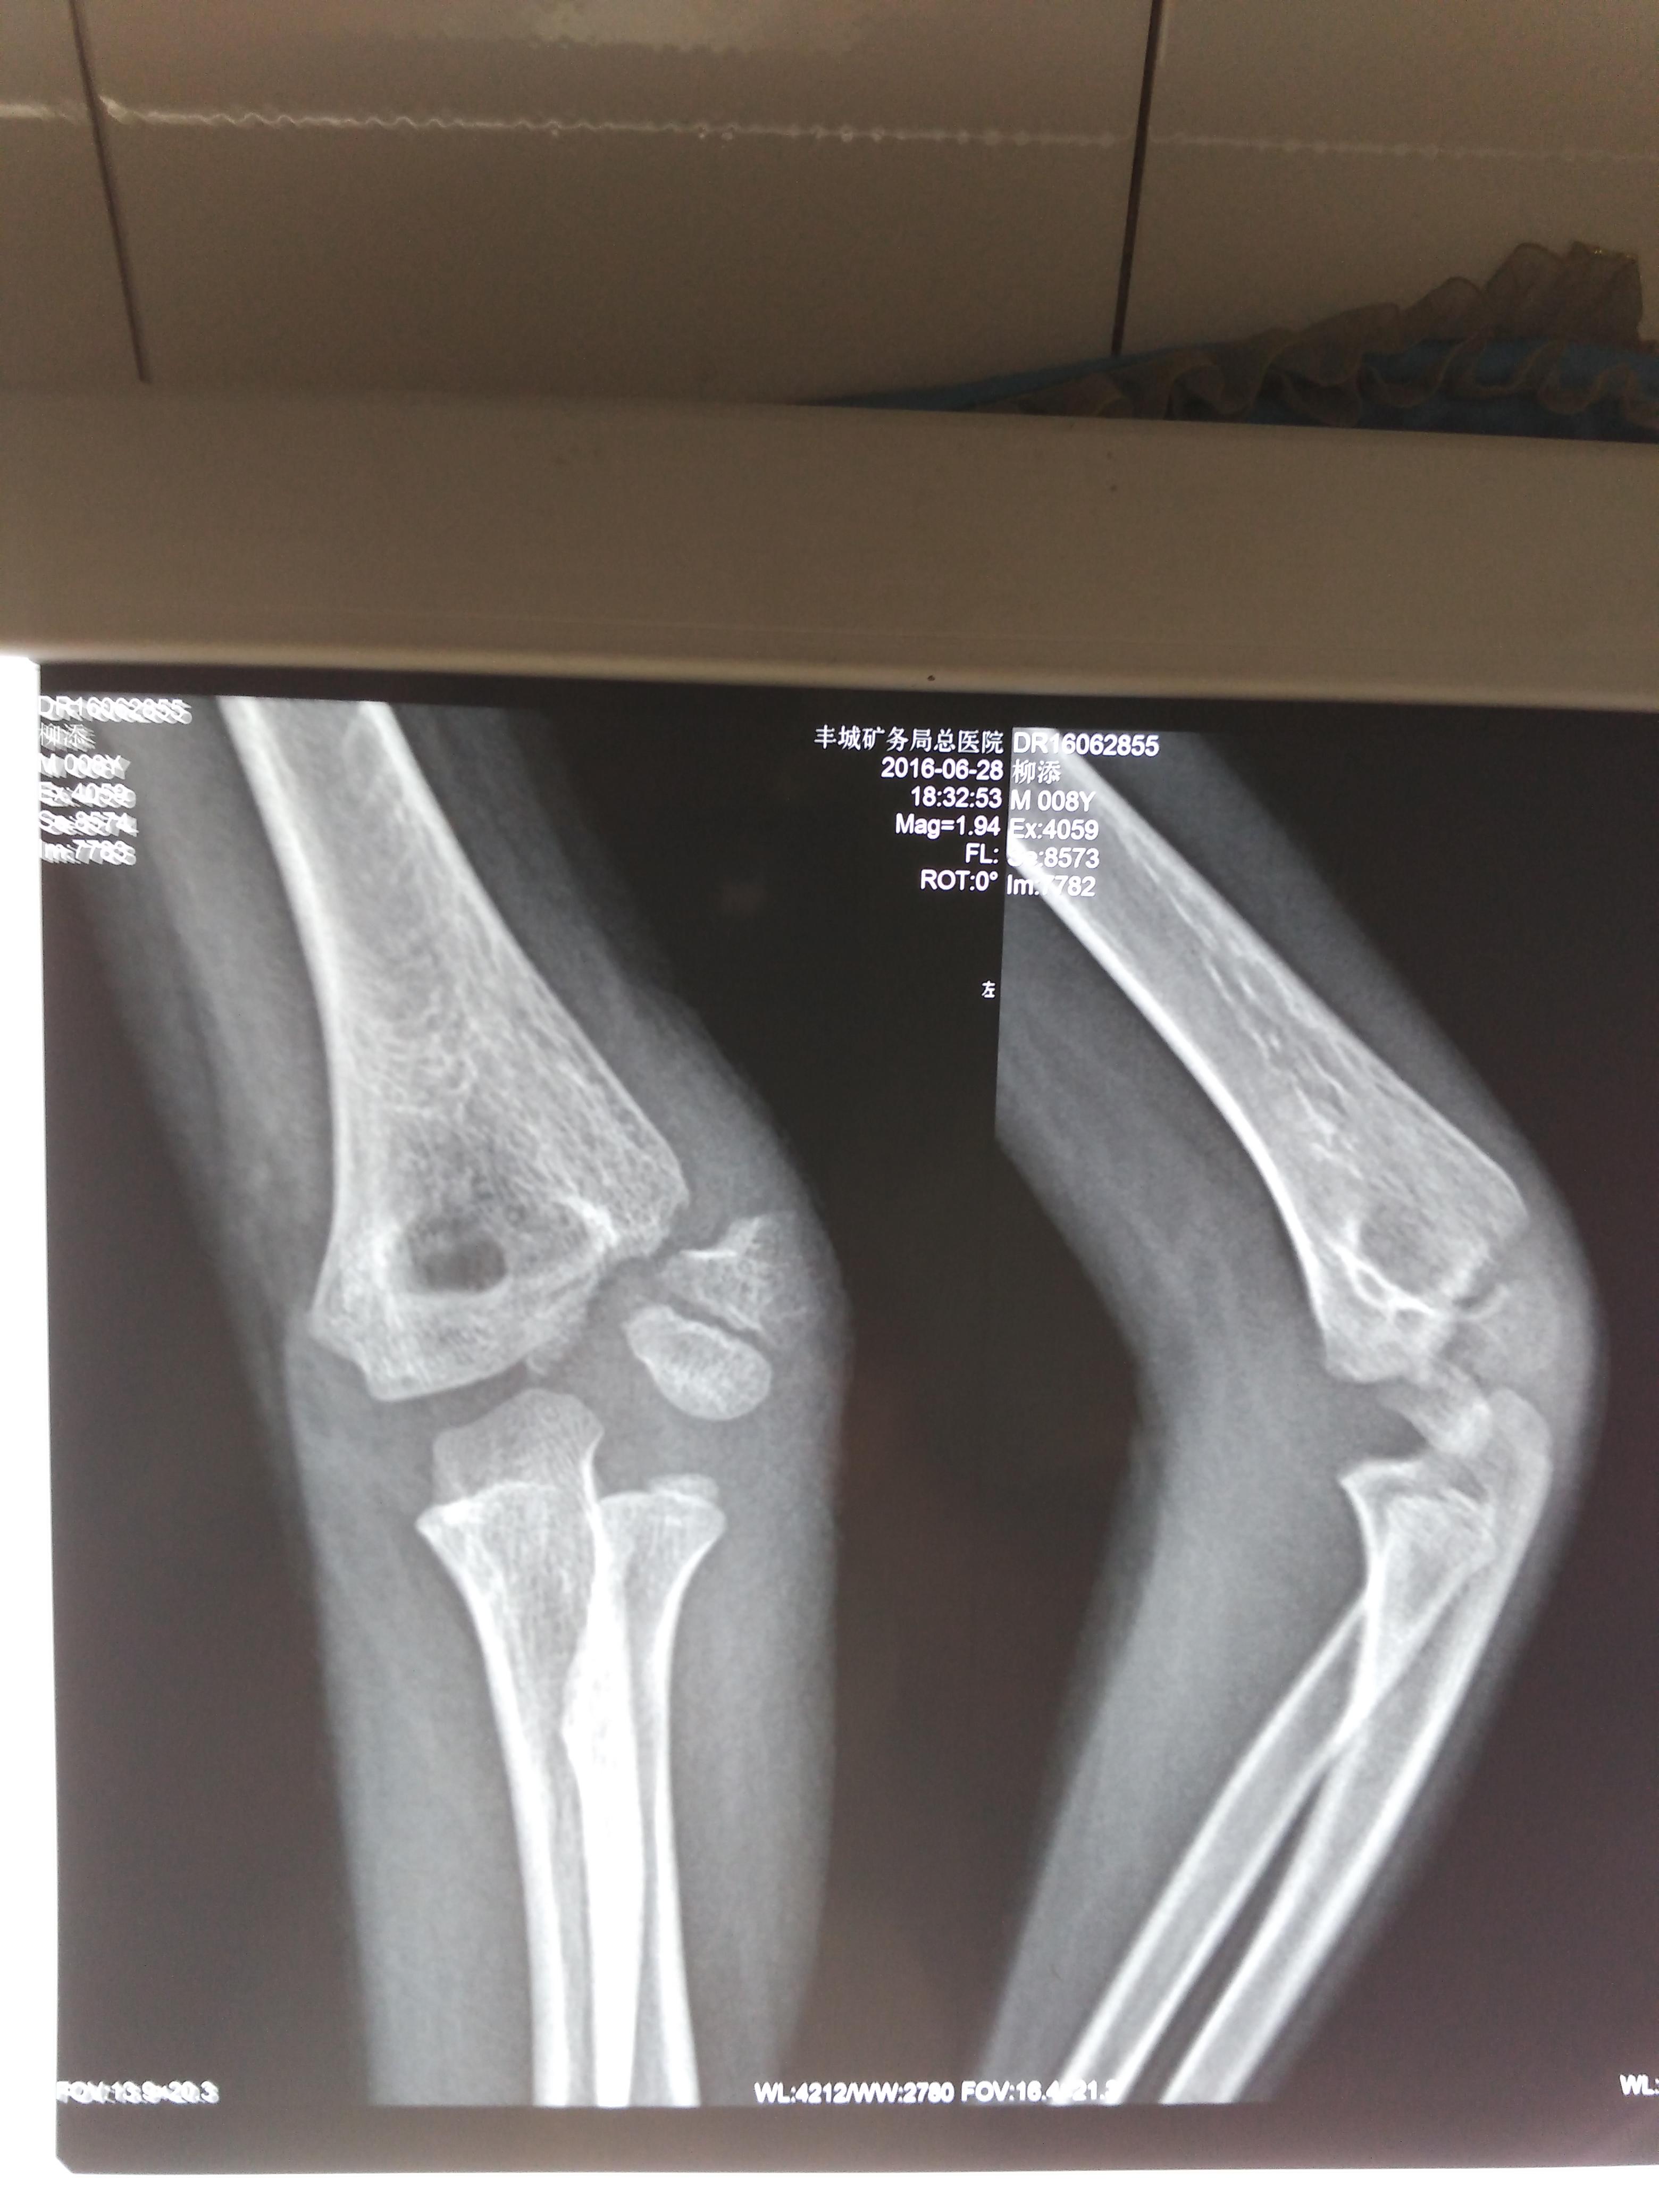

小儿肱骨远端骺离骨折